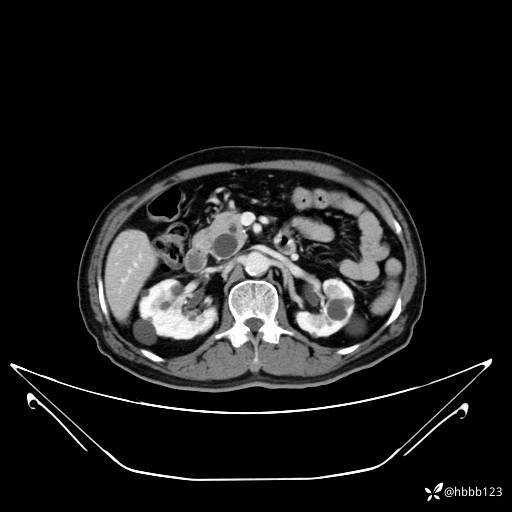

延迟期: